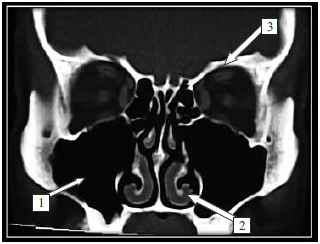

Observe o que segue:

Na imagem radiológica, as estruturas/regiões sinalizadas são, correta e respectivamente,

1: seio maxilar; 2: corneto inferior e 3: porção orbitária do osso frontal.